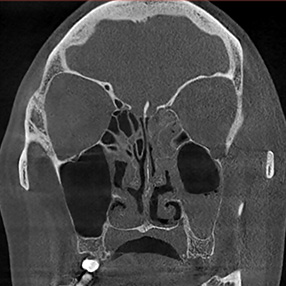

※ 축농증 수술 후 생길 수 있는 부작용으로는 출혈, 감염, 염증이 있을 수 있습니다.

본 사진은 의료기관에서 진료를 본 환자이고, 전후 사진 인물이 동일인이며,동일조건에서 촬영이 되었습니다.